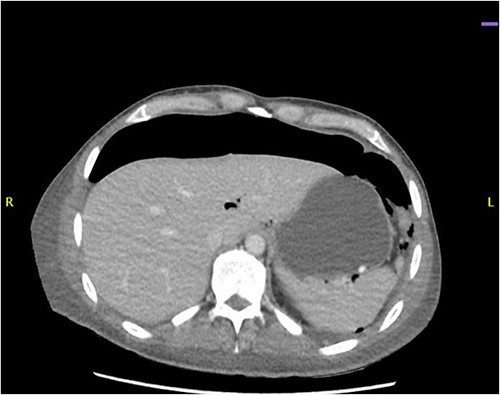

CT abdomen revealed a large amount of free air throughout the abdomen, mostly localized anterior, but also perihepatic, perigastric, paracolic, and perisplenic (Figs 1 and 2).

CT abdomen showing a large amount of free air mostly localized anterior.

CT abdomen showing large amount of free air throughout the abdomen.